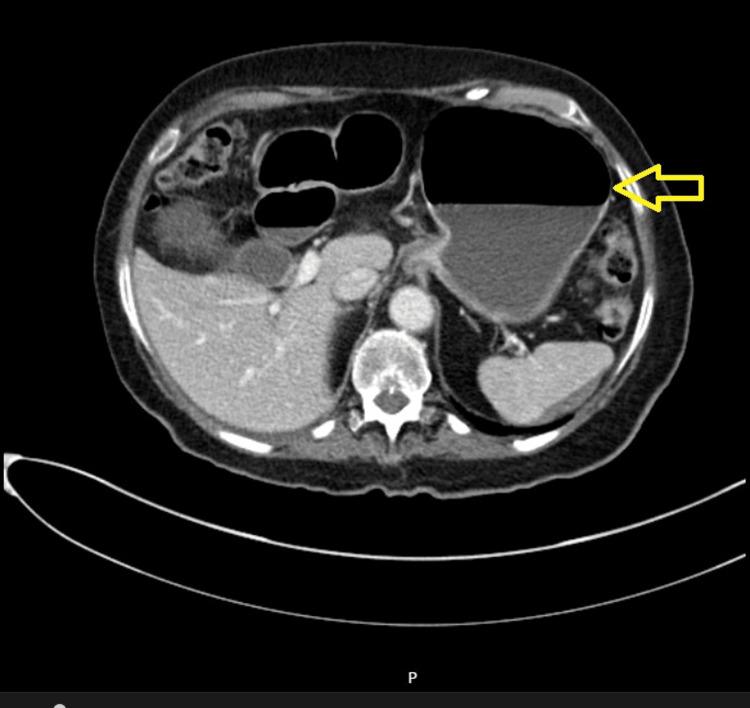

The defining feature across all six cases emerged during exploratory laparotomy, where a consistent finding stunned the surgical team: the discovery of a thick, fibrous membrane enveloping segments of the small bowel. The surgical procedure entailed meticulous dissection and subsequent removal of this membrane, with tissue samples dispatched for histopathological evaluation. This diagnostic approach conclusively confirmed the presence of abdominal cocoon syndrome in each of these patients.

在所有六例病例中,决定性特征在剖腹探查术中显现,一个一致的发现令手术团队震惊:发现一层厚厚的纤维膜包裹着小肠的部分节段。手术过程包括细致的分离并随后移除该膜,组织样本被送去进行组织病理学评估。这种诊断方法最终证实了这些患者均患有腹茧症。